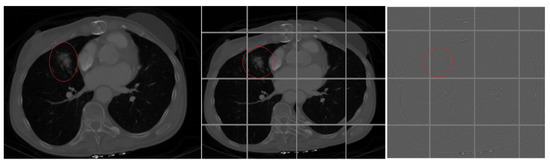

Next, we needed to further group the images in the two piles, where each group represented images from same slice (angle of the chest of the patient). This way, we created 64 groups within each pile, where each group in Pile 1 (cancer pile) had 73 CT images. Each of the 64 groups of Pile 2 (cancer-free pile) had 22 CT images. A sample of different angle (slice) CT images is shown on Figure 2. The middle image is cancer-free (belongs to Pile 2) and the other two are with marked location of the cancer (form Pile 1). Creating the piles of images was done so that we can create positives and negatives to train and test the network, but the groups in each pile were created so that Deep Neural Network would focus on recognizing same slice (angle) images. The groups were created using K-means algorithm to group the image into the appropriate slice group. The reason we used the K-means clustering is because we had CT images that were taken from 16-, 32-, 64-, 128-, 256- and 320-slice CT scanners. We used 64 groups because most of the images we had were 64-sliced. For images obtained from a scanning that made more or fewer than 64 slices, we used the K-means algorithm to put them into the correct group.

Figure 2.

Different angles of CT lung cancer images.